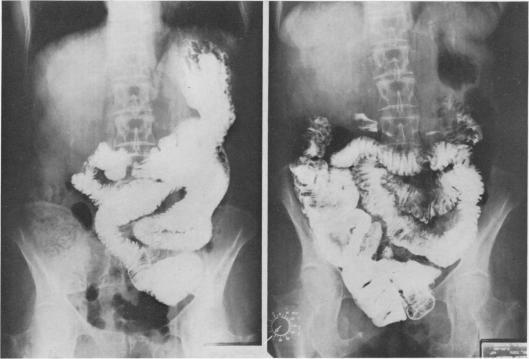

CLINICAL USE OF ANTI-PERISTALTIC BOWEL SEGMENTS.

Ann Surg. 1965 Apr;161(4):601-4. doi: 10.1097/00000658-196504000-00019.